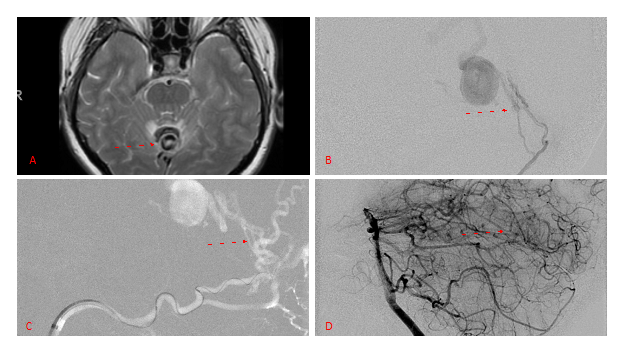

Embolization was successful at immediately reducing the pressure into the Aneurysmal Varix with greater than 90% reduction in A-V shunts. After an intensive period of critical care monitoring and care for her initial brain hemorrhage, she made a near complete recovery with mild intermittent left sided paresthesias and generalized deconditioning. After receiving inpatient and outpatient Acute Rehabilitation, Physical, and Occupational therapy, she completely recovered all of her Activities of Daily Living (ADLs) at 3 months and achieved an modified Rankin Scale (mRS) of 0. On follow-up angiography, small residual low flow A-V shunts were identified and targeted for Gamma Knife Radiosurgery (Figure 5 and 6).

Figure 6. MRI and Catheter Angiograms precisely localize the residual A-V shunts vessels to perform Gamma-Knife Radiosurgery to deliver therapeutic doses to the targets.